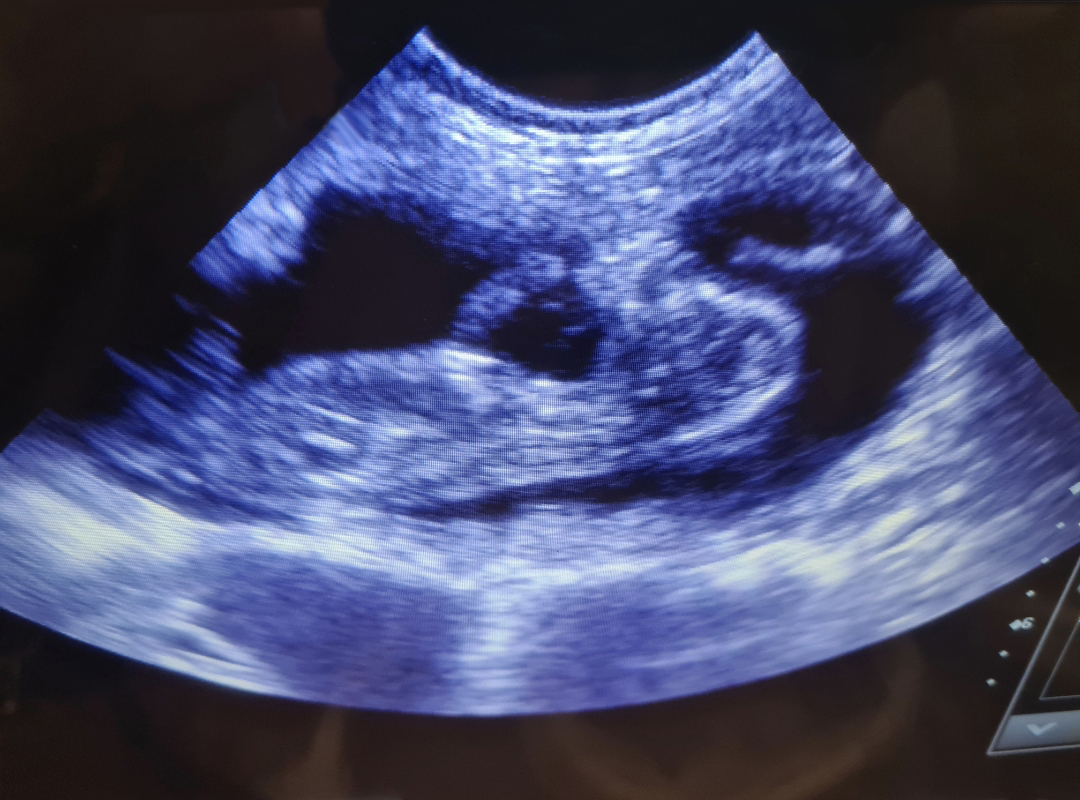

If you believe your pet may be pregnant, we offer gentle and completely painless ultrasound scans to help confirm pregnancy in dogs and cats. These scans can typically be performed from around 28 days after mating.

During the scan, your pet remains calm and comfortable with you gently holding them. A small amount of gel is applied to their abdomen, and a handheld probe is moved carefully over the area to view any developing puppies or kittens.

Using a reliable Scan Pad Ultrasound scanner, Julie can confirm pregnancies and provide you with email copies of any images showing puppies.